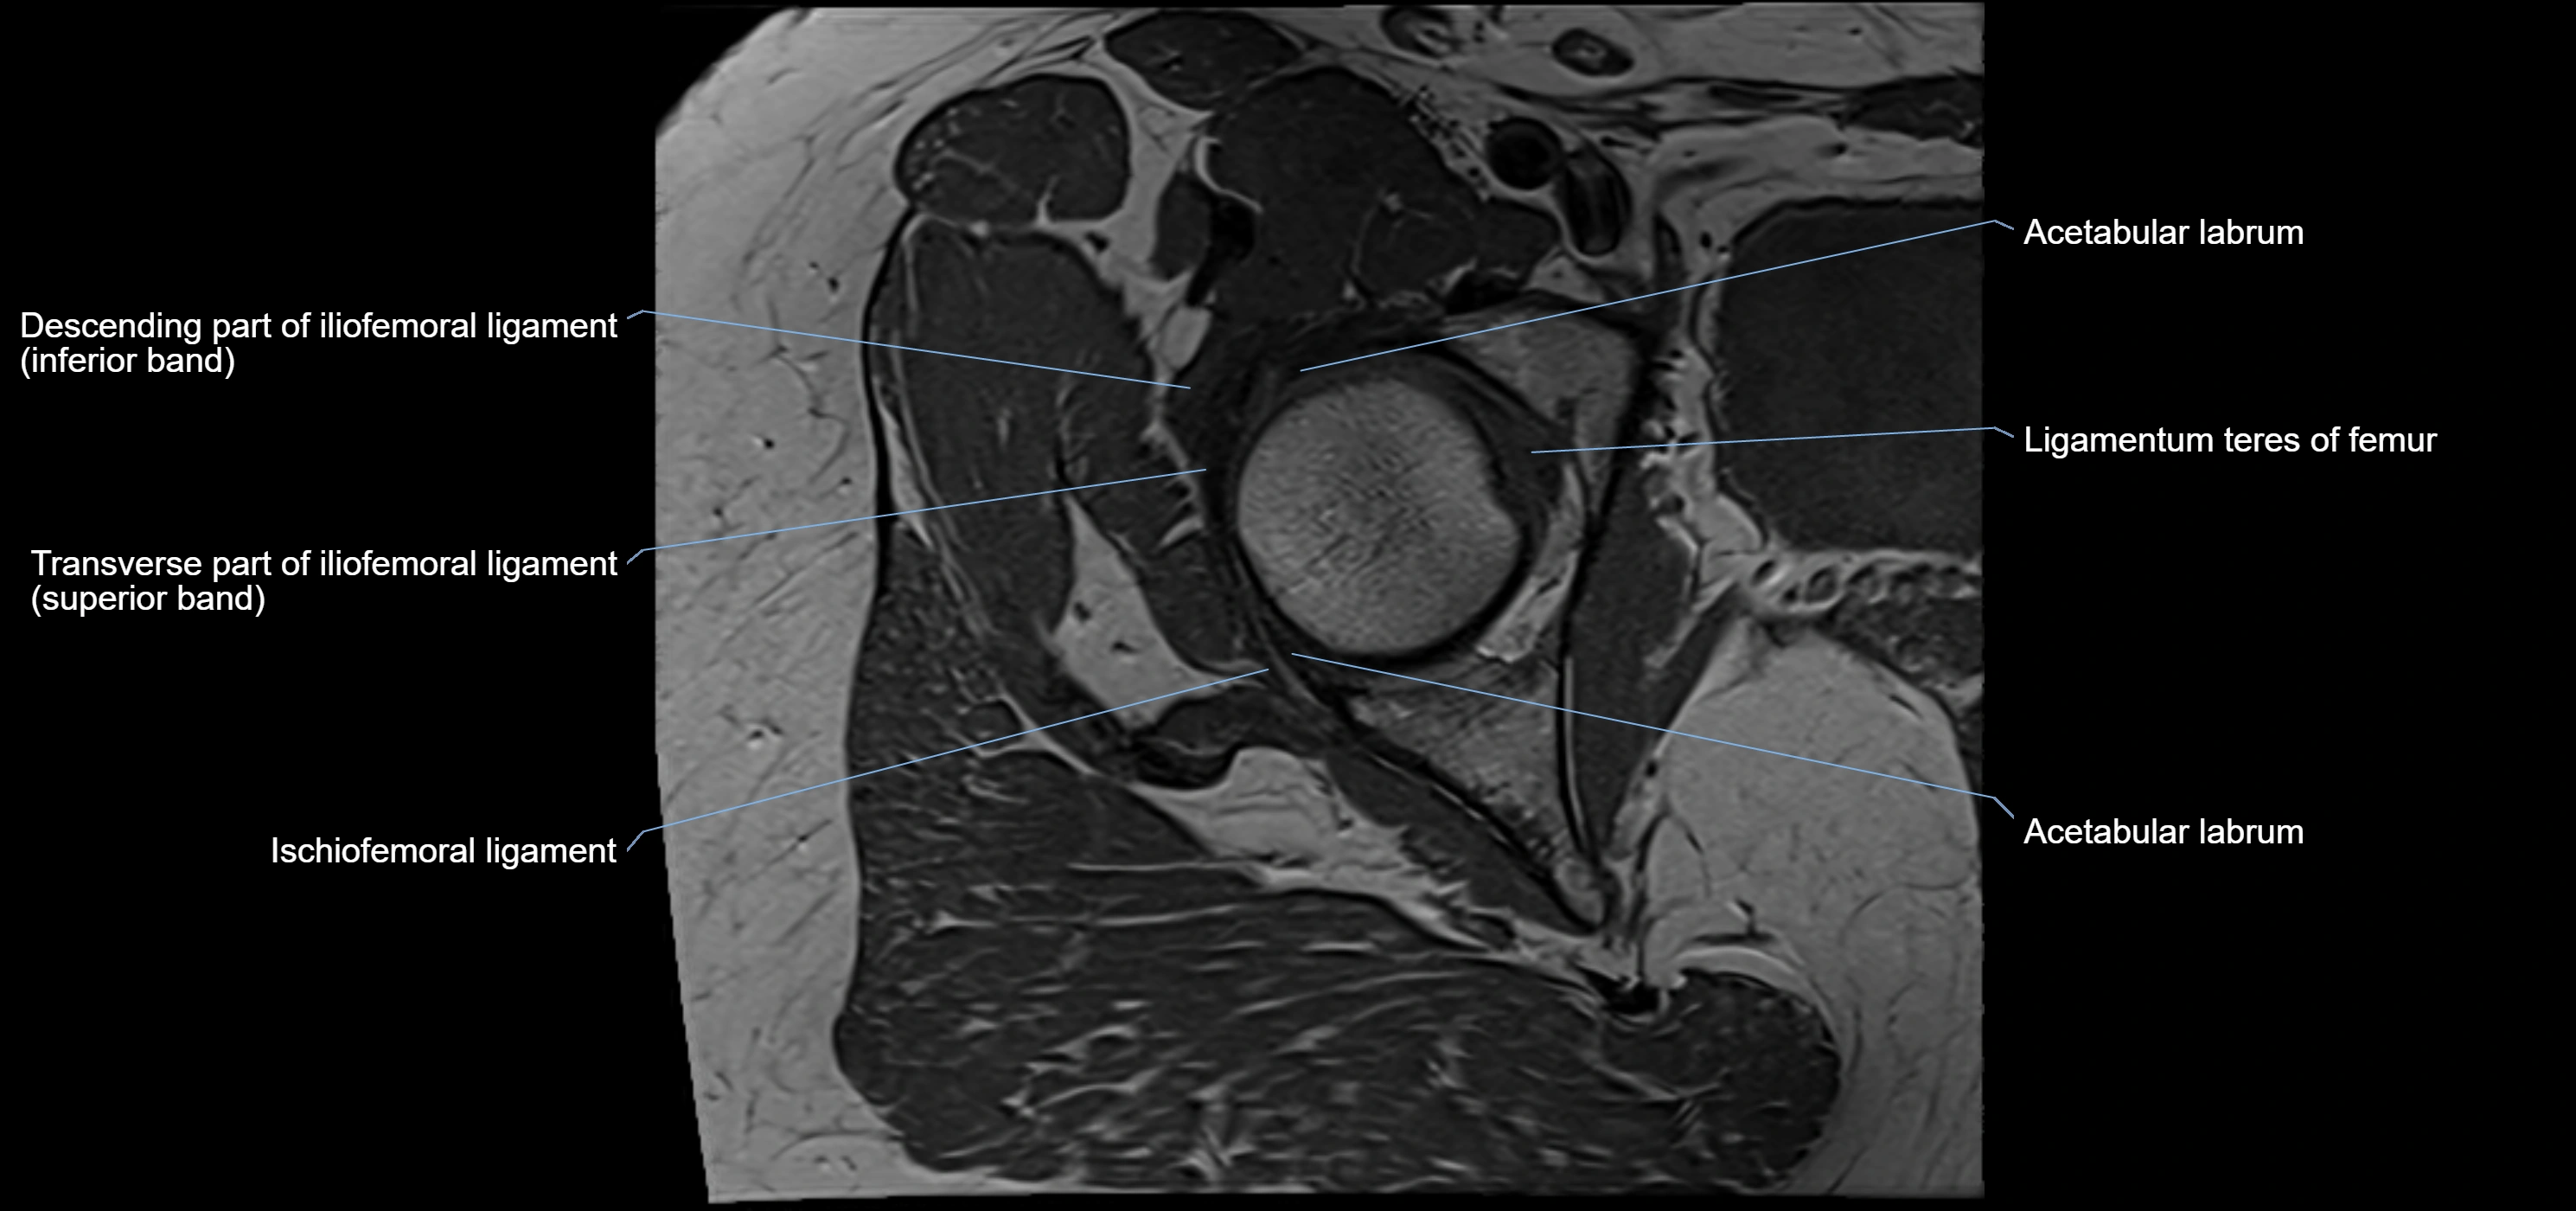

The acetabular labrum is a fibrocartilaginous ring that surrounds the rim of the acetabulum in the hip joint. It deepens the hip socket, increases joint stability, and maintains a suction seal that preserves negative intra-articular pressure. Structurally, the labrum transitions from hyaline cartilage of the acetabulum to dense fibrocartilage at its free edge.

It is triangular in cross-section, with its base attached to the acetabular rim and its apex projecting toward the femoral head. The labrum is most robust superiorly and anteriorly, where load bearing is greatest, and relatively thinner inferiorly.

Structure and Relations

• Superior and anterior labrum: thickest portions, stabilizing against anterior dislocation

• Inferior labrum: blends with the transverse acetabular ligament bridging the acetabular notch

• Relations:

• Medial: acetabular articular cartilage

• Lateral: hip joint capsule

• Inferior: transverse acetabular ligament

• Superior: femoral head

MRI Appearance

T1-weighted images:

• Labrum: low signal intensity (dark)

• Surrounded by intermediate signal joint fluid (bright on arthrogram)

• Tears: linear or focal areas of intermediate-to-high signal interrupting labral continuity

T2-weighted images:

• Joint fluid: bright, making labral tears visible as fluid extending into or around labrum

• Degeneration: may show areas of increased signal within labrum